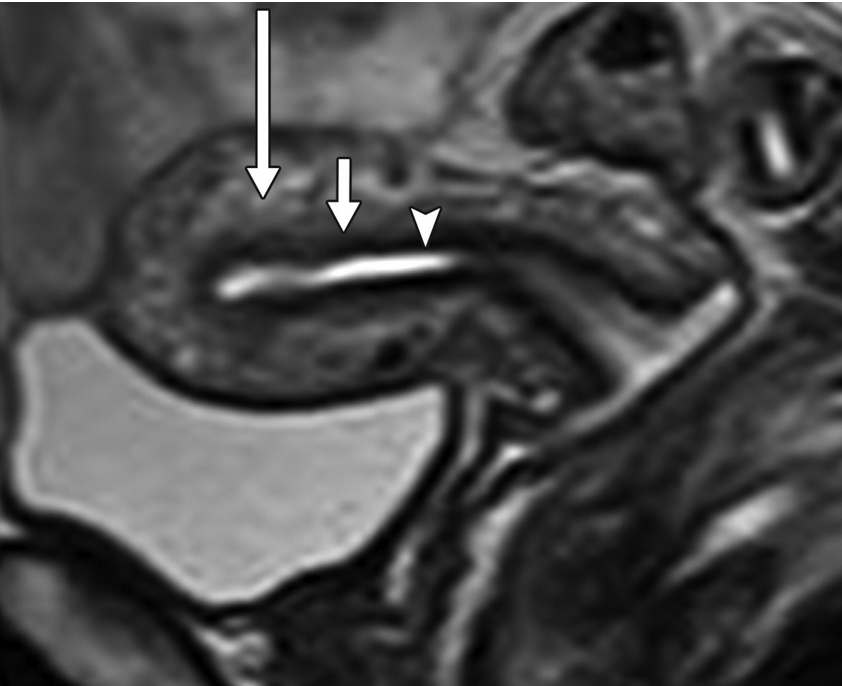

Junctional zone

• Arrow head = endometrium

• Middle arrow = junctional zone

• Long arrow = Outer myometrium